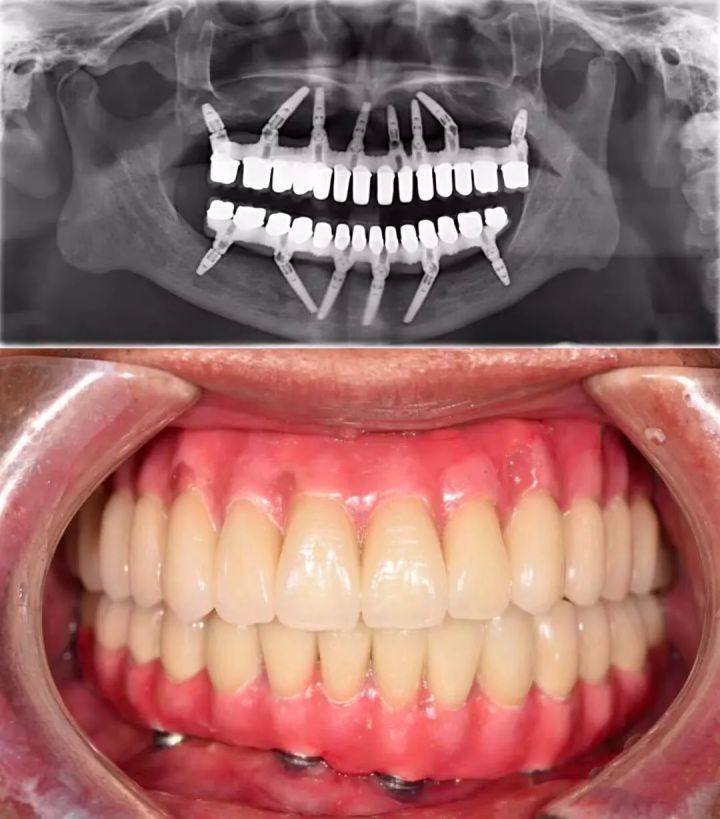

许多患者总认为:牙周炎不是什么大病,能拖就拖,等牙掉光了再镶一口假牙就行。殊不知全*活口**动义齿,不仅功能比天然牙齿相差一大截,咀嚼效力不高,使用也不方便。全口种植义齿也是一种选择,可以较好地恢复咀嚼功能。

但现实是,并不是每个无牙患者,都拥有「口腔里开一辆奔驰」的财力。

价格高昂种植义齿